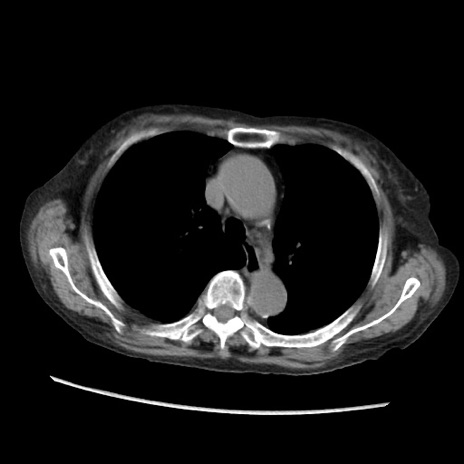

矢状断像

【症例】80歳代 女性

【主訴】腹部膨満感

【現病歴】他院にて肝硬変にてフォロー中。1週間前から便秘、腹部膨満感、臍部腫瘤あり受診となる。

【既往歴】肝硬変

【身体所見】腹部膨隆あり、皮膚変化なし、疼痛なし。

【データ】WBC 4600、CRP 0.25